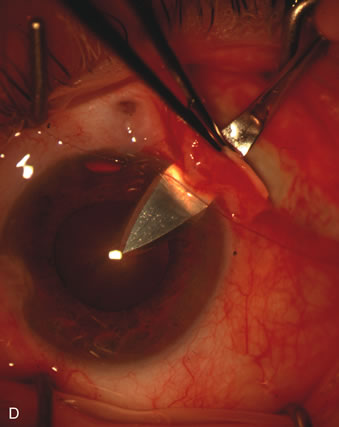

CASE 6: ANTICIPATED LENS EXTRACTION POST FAILED TRABECULECTOMY WITH ADVANCED DISC DAMAGE AND IOP OUTSIDE TARGET PRESSURE RANGE

The inflammation associated with lens extraction at any site usually causes complete failure of a marginal functioning bleb. In addition, pressure reduction by medical means is usually minimal in these recalcitrant cases, and combined surgery is indicated. In the past, these cases were approached with large-incision ECCE, clear corneal cataract incision, and bleb revision. Drawbacks included those mentioned earlier for large incision clear corneal cataract extraction, and bleb revision is often associated with conjunctival buttonholes, wound leaks, subconjunctival hematoma, destruction of friable sclera, and associated hypotony. With the advent of modern-day cataract surgery, a phacotrabeculectomy is often possible adjacent to the failed filter (Fig. 7). The ability to combine cataract extraction with implant and filtration surgery all through the same small incision has greatly improved outcomes for patients with marginal preoperative filters. There are several other viable options in this case. If the surgeon elects to remove the cataract through a temporal clear corneal incision, the bleb may be revised or a new adjacent filter fashioned. As mentioned earlier, revising a failed filter is technically challenging. If the surgeon believes it is not feasible to revise the filter or fashion a new one, a glaucoma drainage implant is a reasonable option combined with temporal lens extraction.172

Fig. 7. Phacotrabeculectomy adjacent to a failed filter in cataractous eye. The ability to combine small-incision cataract extraction with trabeculectomy all through the same incision adjacent to the failed filter allows the surgeon to work in a familiar superior area. Avoiding incisions into the existing bleb decreases conjunctival buttonholes, hypotony, operating room time, and subconjunctival bleeding. A. Appearance of failed bleb with exposure of superior temporal quadrant gained with a corneal traction suture. B. Prepare a limbus-based conjunctival flap and a scleral flap. C. This bleb is at high risk to fail again justifying the need for MMC, 0.2 mg/cc applied on a pledget for 4 minutes. D. Insert the keratome and perform phacotrabeculectomy in the usual fashion.